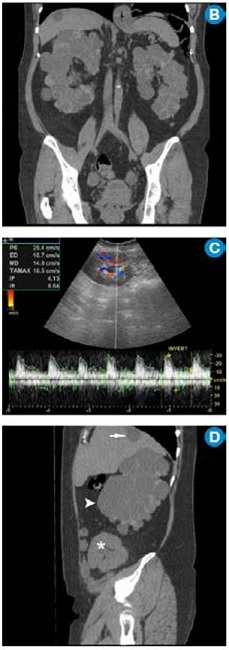

Por su alta sensibilidad, disponibilidad y bajo costo, la ecografía renal es el estudio inicial con el que se pueden observar riñones grandes con quistes bilaterales, múltiples y tamaño variable (figura 1); sin embargo, es altamente dependiente del operador y es menos sensible para detectar quistes <1cm que se visualizan mejor en la escanografía o en la resonancia magnética 24. Pese a que en la actualidad no existen criterios estandarizados en estas dos técnicas imagenológicas para el diagnóstico de la PKD, la tomografía computarizada (TC) y la resonancia magnética (RM) son más sensibles para el diagnóstico de los quistes en los casos dudosos, la detección de complicaciones, la valoración de la progresión y la respuesta al tratamiento 25 (figura 2).

En la ARPKD, el diagnóstico puede ser realizado en el período intrauterino, neonatal o en los primeros meses de vida por medio de una ecografía renal en la que se observan los riñones aumentados de tamaño, con pérdida de la relación corticomedular, hipoplasia pulmonar y oligohidramnios debido al bajo gasto urinario 31. En edades posteriores se prefieren las imágenes por TC y RM para seguimiento o, como ya se mencionó, para casos dudosos. En las fases tempranas, los riñones pueden ser de tamaño y forma normal; en las fases posteriores aumenta el número y el tamaño de los quistes, con distribución difusa del parénquima, aumento del tamaño (se alcanzan longitudes de hasta 40cm) y, por consiguiente, aumento del volumen renal. La RM es la técnica de elección empleada para la volumetría de los quistes y del parénquima como indicadores de progresión o de respuesta al tratamiento.